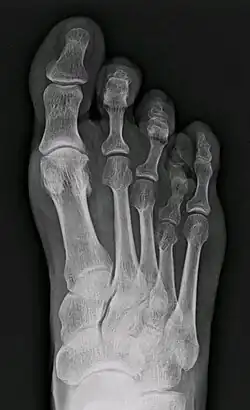

Brachymetatarsie

Am häufigsten ist der erste Mittelfußknochen betroffen, wodurch die Großzehe deutlich kürzer ist und der normale Abrollvorgang des Fußes über den Großzehenballen gestört ist und es somit zu einer Mehrbelastung der zweiten und dritten Zehe und einer Metatarsalgie (Vorfußschmerzen) durch Störung des sog. Quergewölbes kommen kann. Allerdings ist der erste Mittelfußknochen bei 40 % aller Menschen leicht kürzer als der zweite Mittelfußknochen, erst bei einer wesentlichen Verkürzung liegt eine Brachymetatarsie I vor.[4]

Daneben können auch alle anderen Mittelfußknochen betroffen sein, der vierte ist neben dem ersten der häufigste verkürzte Mittelfußknochen. Dabei steht die eigentlich nicht verkürzte Zehe mit ihrer körpernäheren (proximaleren) Basis aber nach oben über liegt auf den benachbarten Zehen und bildet manchmal Druckstellen. Dies ist aber oft mehr ein kosmetisches als ein orthopädisches Problem.